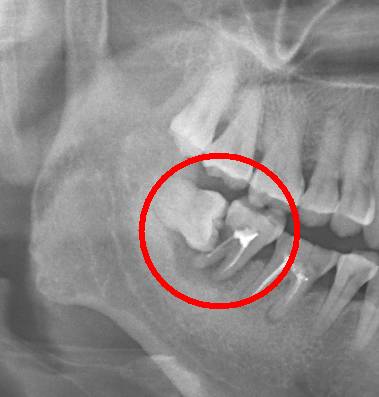

阻生智齿中典型的“秀恩爱,死得快”型,智齿因为萌出空间不足,造成倾斜阻生,斜靠在旁边的牙齿上,把旁边好好的邻牙给直接顶坏掉。

口说无凭,上病例。来看下面这例

这种情况就因为没及时拔除智齿,最终的结果就是把邻牙也拖下水,两颗牙齿一起报销,旁边的第二恒磨牙本来就容易因为清洁不彻底龋坏的好么,还要无端被拖着陪葬,真是生存不易。更惨的是,邻牙拔除之后,还必需要装上一颗种植牙补上(我会告诉你装一颗种植牙花费上万是很正常的么),得不偿失啊!!

下面这例又是一个悲伤的故事:

需要特别注意的是,邻牙病变具有一定的隐蔽性,通常的情况是可能旁边牙齿已经被顶坏了,患者还没有任何感觉,这就需要拍一张口腔 X 光片才能进行准确的诊断。